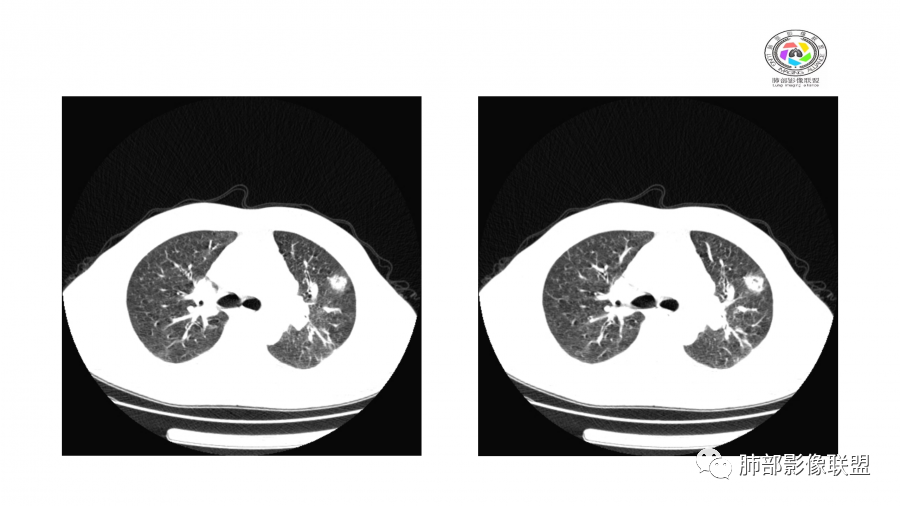

患者,男,49岁,初次以头晕呕吐肾功能异常入院,后期伴双下肢水肿,CT示双肺多发斑片及结节影,部分周围伴晕,部分内部可见支气管穿行,多次复查可见部分病灶略吸收及新发病灶出现,最后一次复查双肺多发磨玻璃样改变,综合考虑血管炎,最后一次伴肺水肿可能

影像:双肺散在实变影及毛玻璃影,实性病变周围可见晕征,病灶于肺外围区域优势分布,病变区引流支气管未见增厚,考虑血管相关病变;3月、4月复查CT提示肺内病灶呈游走性,此起彼伏。

中年男性,肾功能异常,双肺多发结节及磨玻璃影,边界欠清,部分可见小叶间隔增厚,可见支气管及血管穿行病灶内,复查发现,病灶有吸收又有新发,考虑GPA,OP。鉴别病毒感染

胸部CT:双肺多发实性斑片影,散在GGO。实性斑片周围可见晕征、边缘模糊不清,病灶于肺外围区域优势分布。肺门区血管影增粗,支气管套袖,目测肺动脉增粗。3月、4月复查肺内实性斑片病灶呈游走性,此起彼伏。

双肺多发斑片及结节状磨玻璃影,部分内部可见支气管穿行,多次复查可见部分病灶略吸收及新发病灶出现,肾功能不全,贫血,综合考虑肺泡出血,血管炎。

谢加平:

双肺多发斑片影,沿支气管血束分布,前后复查对比,大部分有吸收好转,另外新发(此起彼伏特点),患者肾功能不全及肾性高血压,首选血管炎,并肺泡出血可能。